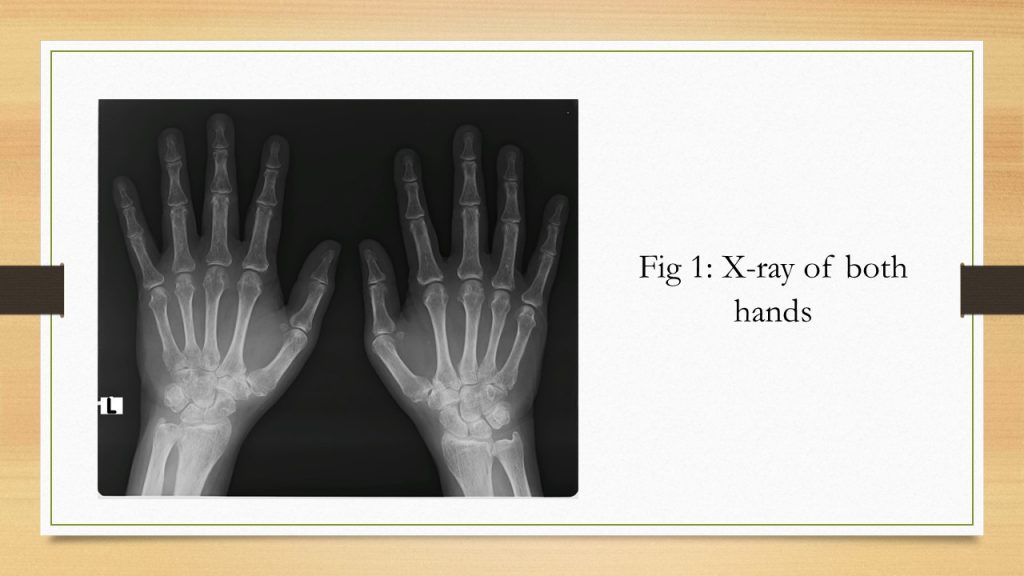

The current case fulfills the ACR/EULAR 2010 criteria for diagnosing RA1, with joint involvement scoring 5, elevated ESR and CRP scoring 1, and more than 6 weeks scoring 7. However, since both the antibody profiles are negative and the patient is aged, it is significant to consider the possibility of other diseases. The patient had the severe proximal joint disease and ESR was more than 100. When the 2012 revised EULAR/ACR criteria for polymyalgia rheumatic (PMR) are considered, the patient fulfilled all the essential criteria like age above 50 yrs, recent onset bilateral shoulder pain, and elevated ESR and CRP.2 He gets a score of 4 in non-ultrasound criteria, based on the presence of stiffness throughout the day and absence of anti-CCP antibodies (ACCPA) and RF. The unusual symptom noticed is the occurrence of peripheral arthritis in small joints of hands and feet. As per the patient history, the disease of the hand is more than 7 years old, and the X-ray demonstrated more osteoarthritis changes than RA. These findings suggest the possibility of having PMR than RA.